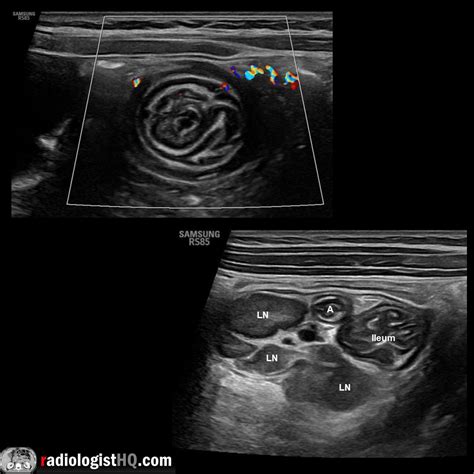

Ultrasound is a valuable tool for diagnosing intussusception, especially in pediatric patients. It provides real-time imaging and can detect the characteristic “target” or “doughnut” sign, which indicates the presence of intussusception. The ultrasound probe is placed on the abdomen, and the radiologist looks for the following signs:

• Target Sign: A hypoechoic outer ring surrounding a hyperechoic inner ring, resembling a target.

• Doughnut Sign: A similar appearance to the target sign but viewed in a transverse section.

• Pseudo-Kidney Sign: An elongated, oval structure resembling a kidney, seen in longitudinal sections.